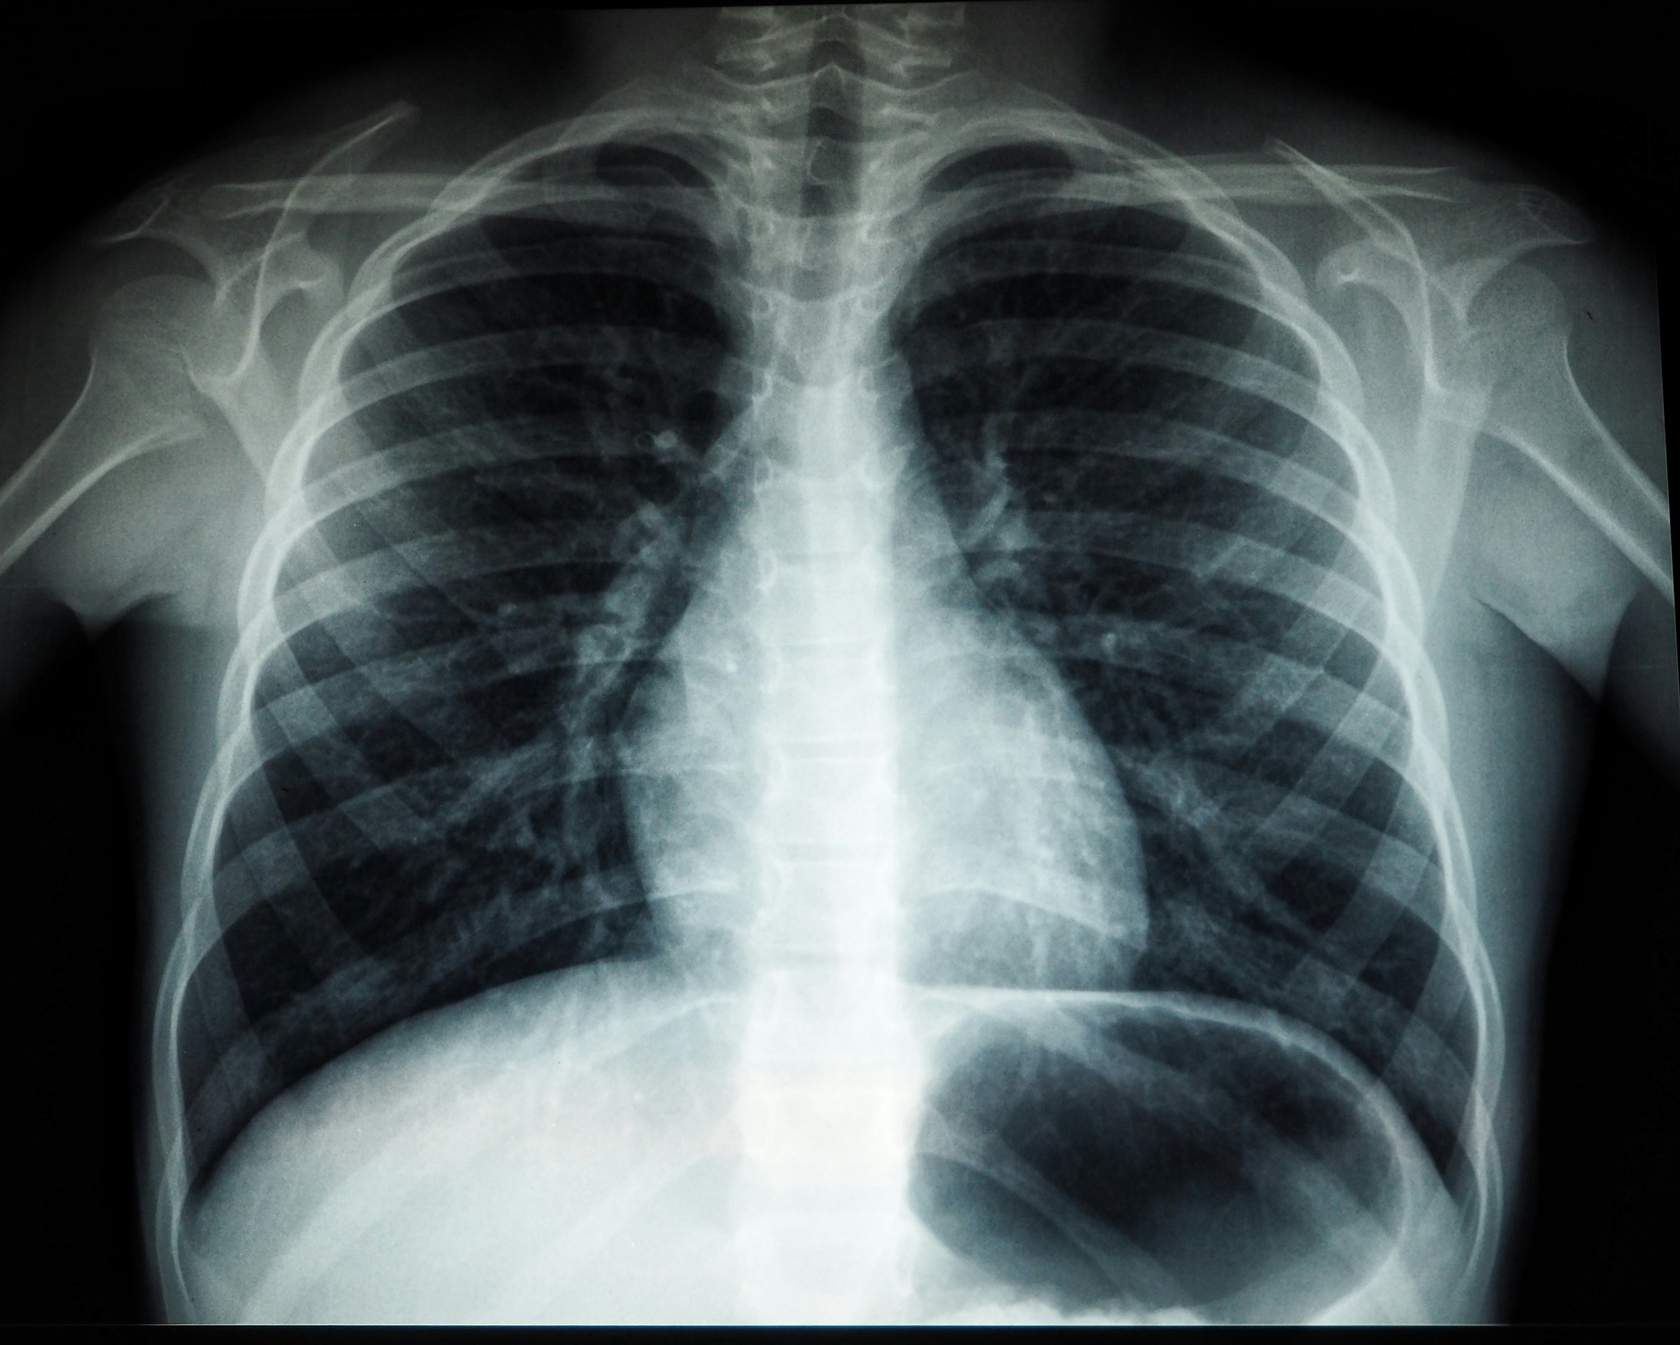

Entregar conocimientos y contribuir al desarrollo de competencias que permitan identificar signos y patrones radiológicos con el objeto de mejorar su interpretación y realizar un diagnóstico más adecuado de las principales patologías respiratorias.

- Adquirir conocimientos actualizados que permitan la correcta lectura de las distintas proyecciones radiológicas torácicas siendo capaz de reconocer los distintos segmentos pulmonares y su ubicación radiológica.

- Incorporar a la práctica clínica una sistemática de lectura e interpretación de la radiografía de tórax, como medio diagnóstico en la patología respiratoria.

- Adquirir los conocimientos anatómicos necesarios que permitan al facultativo distinguir patrones radiológicos alterados frente a los patrones normales de una radiografía de tórax, en el adulto y en el niño sanos.

- Distinguir entre los distintos signos radiológicos en la radiografía de tórax.

- Brindar los conocimientos necesarios para establecer un diagnóstico preciso en las patologías respiratorias más relevantes, interpretando correctamente los hallazgos radiológicos encontrados en una radiografía de tórax.